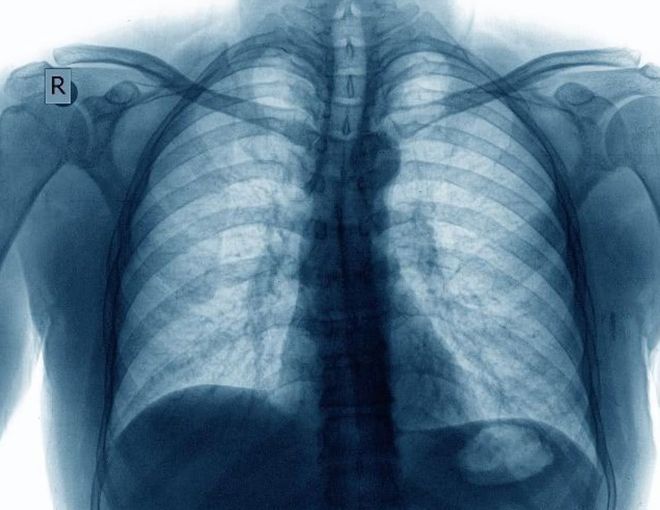

从上图拍摄的胸透CT影像,可以清晰的看到肋骨、骨骼等组织,如果胸腔有病变,则胸腔位置会出现异常影像,医生就是根据这个来判断是否存在组织病变,以确定是否需要进一步检查。这个和工业XRAY检查机的原理是一致的。